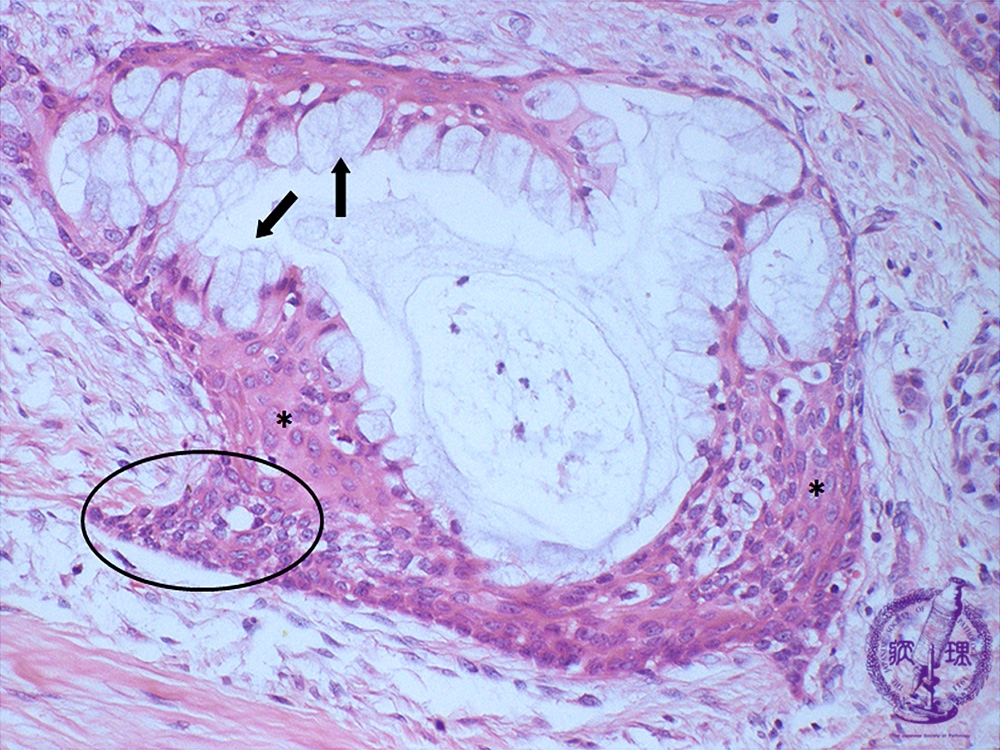

Microscopic finding (HE stain, high-power view):The tumor nests consist predominantly of mucus producing (arrows) and epidermal (*) cells. Cellular atypia and mitotic figures are inconspicuous. A small number of compact and less differentiated intermediate cells (within the circle) are also observed.